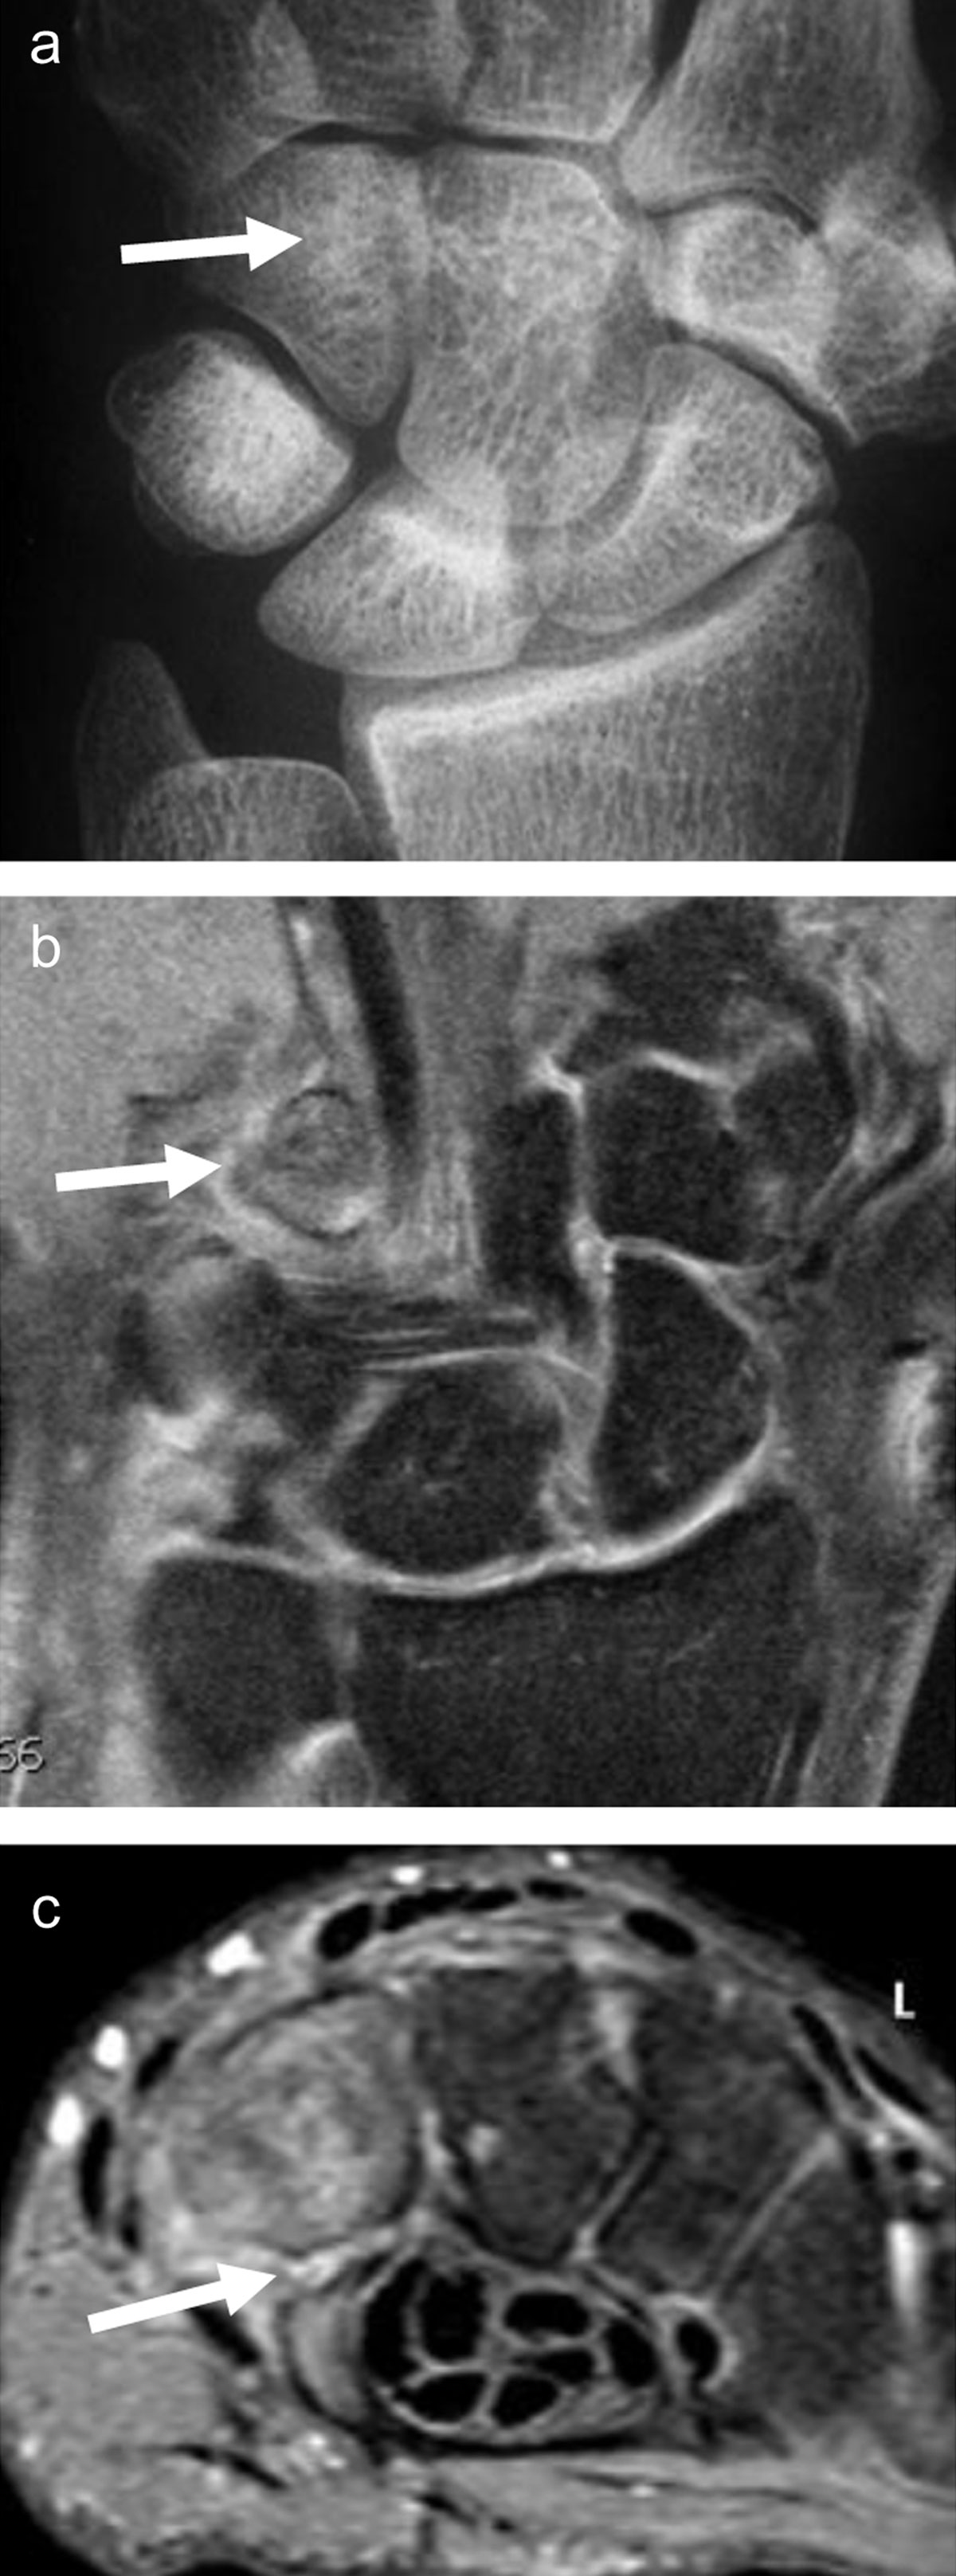

Figure 6

Fracture of the hook of the hamatum, easily missed on conventional radiographs and on fat-saturated MR images. The AP X-ray (a, arrow) demonstrates the absence of the ring sign (normally present at the level of the hamulus) on the hamate bone. On palmar proton-density fat-saturated coronal image (b, arrow), the presence of BME within the hamulus may be obscured because of the close signal intensity of the surrounding muscles. The fracture line at the base of the hamulus could also be missed on the axial proton-density fat-saturated sequence (c, arrow).